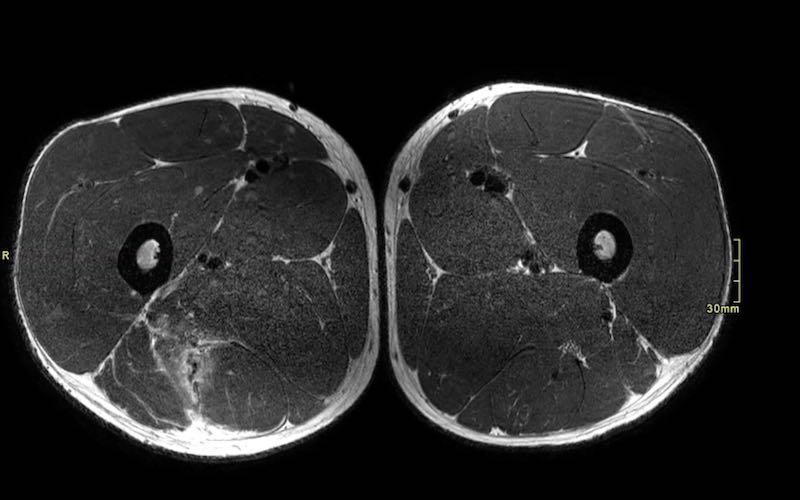

Trên các hình ảnh axial này, có thể thấy tăng tín hiệu và dày lên của gân cơ nhị đầu đùi bên trái (vòng tròn chấm vàng) khi so sánh với bên không bị tổn thương (vòng tròn chấm trắng).

Tại đây bạn có thể cuộn qua các hình ảnh axial. Có thể phóng to hình ảnh bằng cách nhấp vào chúng.

Đây là tổn thương bán phần, bắt đầu từ gân chung ở phía gần, bao gồm cả vùng MTJ và gân trong cơ ở phía xa hơn. Chiều dài vùng phù nề và mức độ biến dạng gân đều ở mức độ cao. Trường hợp này được phân loại là tổn thương BAMIC 3b/c.